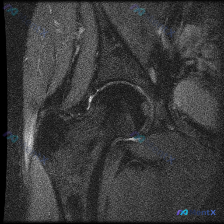

今天看到一个很有讨论价值的读片病例,整理一下信息和分析思路给大家参考。 病例基本信息 问题:患者主诉踝关节感觉有软组织积液,请读片判断 影像:踝关节MRI-脂肪抑制序列-轴位单张图像 影像详细评估 这是踝关节远端水平的轴位扫描,先给大家整理一下观察结果: 1. 骨骼:胫骨远端、腓骨远端骨髓信号正常,...

看到一份只有踝关节MRI影像的病例,这里给大家整理一下读片思路和容易踩的坑,一起来讨论下。 病例核心信息: 这是踝关节MRI-T2序列轴位图像,主要的异常发现如下: 1. 解剖结构基本正常:跟腱、腓骨长短肌腱、内踝后方各肌腱走行连续,信号都正常;距骨、跟骨骨髓信号没有异常水肿或破坏,没有骨折或明显韧...

拿到这张踝关节MRI T2轴位片,问题问软组织液有什么表现,整理一下病例信息和分析思路给大家参考: 基本影像信息 这是踝关节MRI T2序列轴位图像,核心发现是: 1. 骨骼:距骨等主要骨性结构轮廓连续,无明显骨皮质中断,骨髓无大范围明显T2高信号水肿 2. 肌腱韧带:外侧腓骨长短肌腱走行区可见不规...